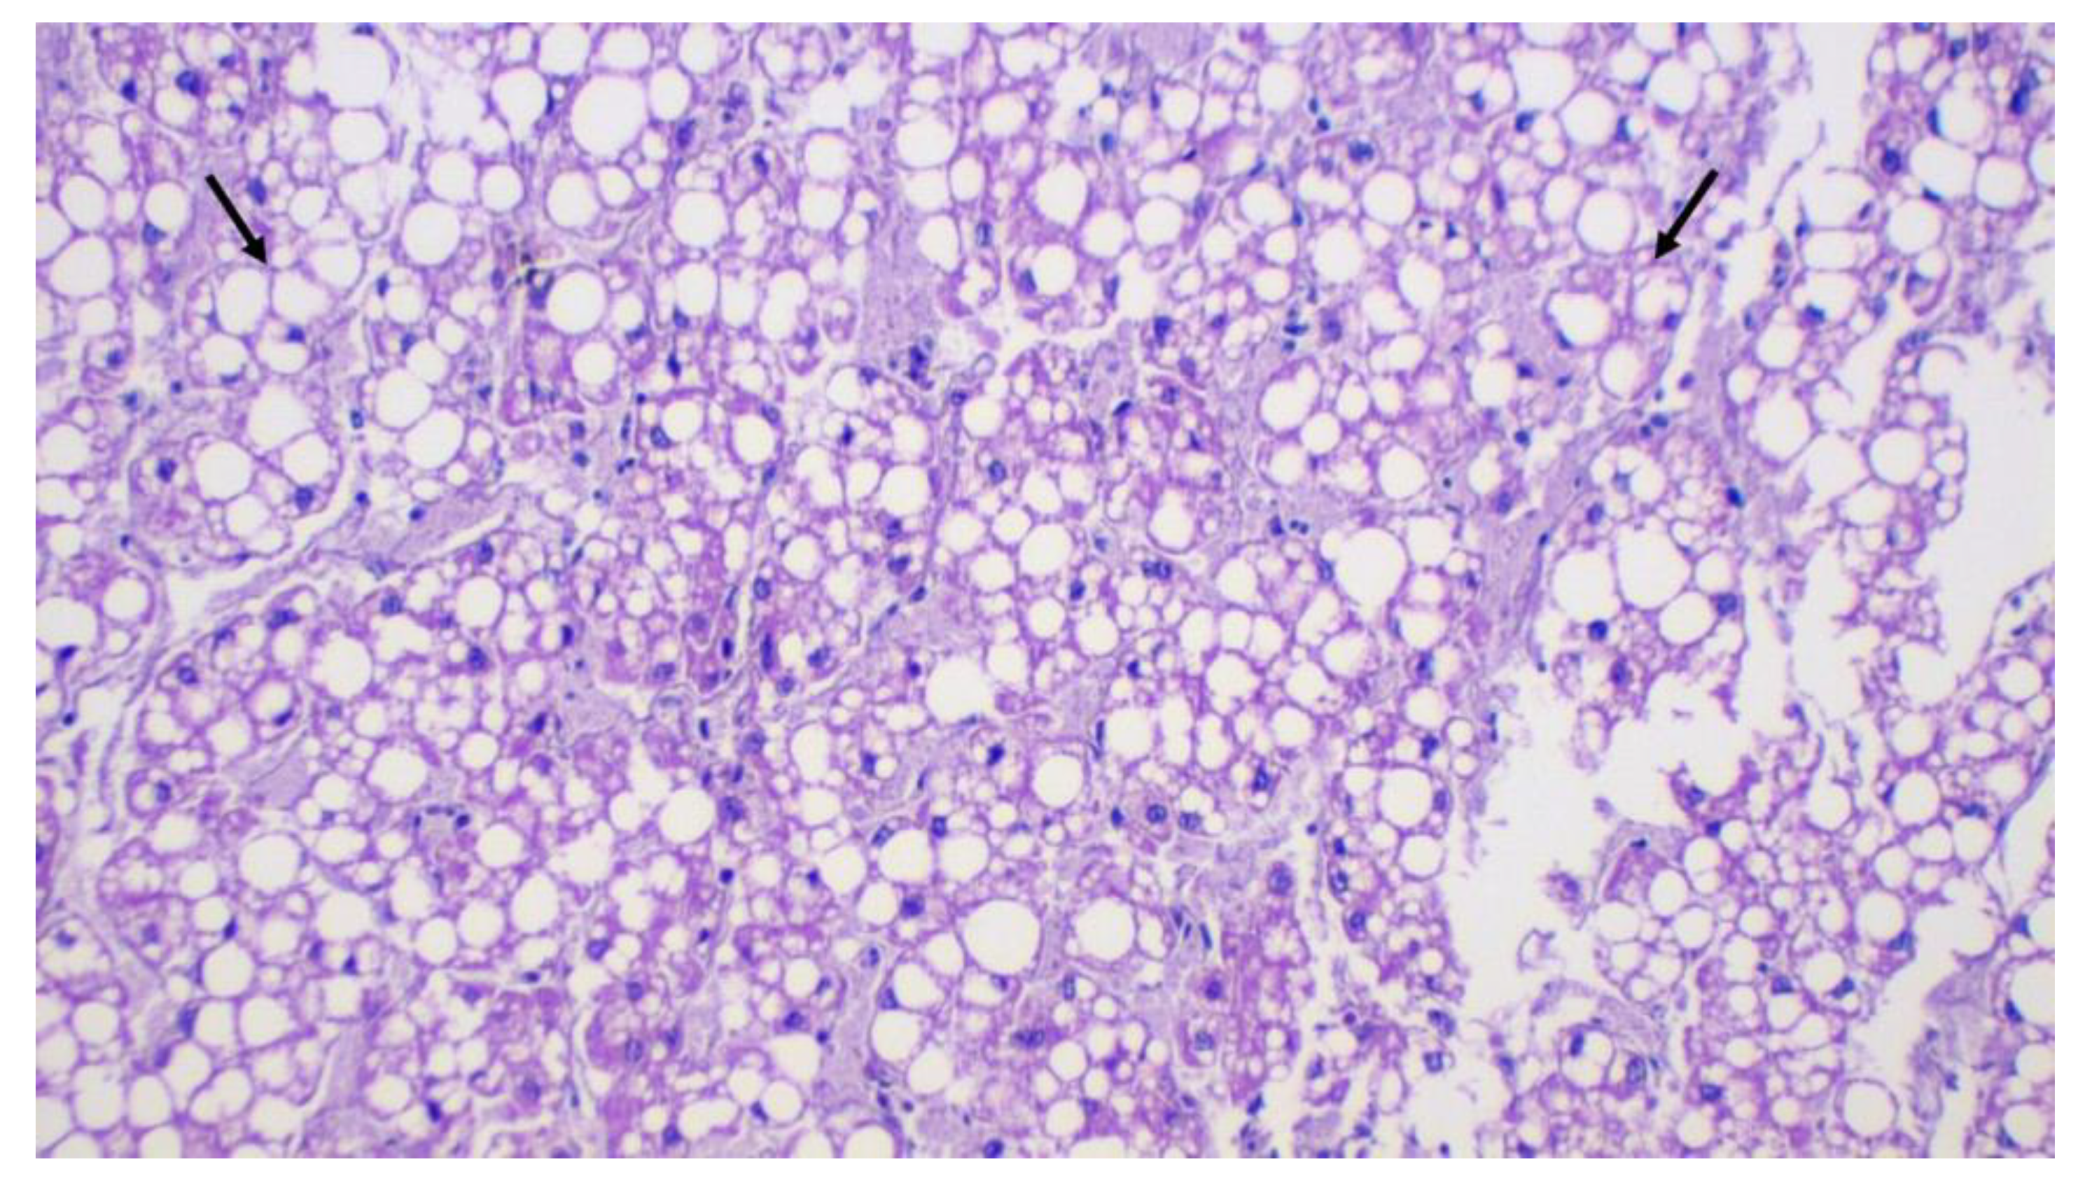

2.4. Liver and Gallbladder Histopathology